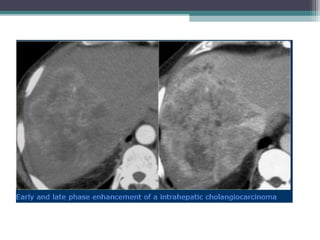

• CT:

Hypodense solitary mas with satellite nodules

Post con : Thin rim/Thick band of peripheral and patchy

enhancement . The central area of tumour , which contains fibrous

tissues does not enhance during early phase but shows progressive

centripetal enhacement and retension on delayed images during

delayed phase 4-20min ( Helps to dfferenciae from HCC )